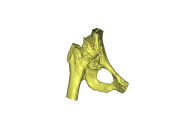

但传统X线、CT、MRI等检查在了解髋臼缺损方面不够全面、精准、直观,在手术方案确定和假体选择上都给医生出了难题。为此,大家决定借助“神器”3D打印技术,以1:1再现患者的病患髋关节,以便精准制定手术方案。与此同时,项目组成员迅速联系影像中心获取了患髋CT数据并使用MIMICS软件重建患髋三维图像并使用3D打印技术1:1再现患者的髋关节,根据髋关节模型,项目组再次详细致地讨论了手术方案,并在术前与患者及其家属通过3D模型直观的介绍患者的病变以及手术的方案,获得了患者及家属的理解和支持。

3D打印技术在人工关节置换手术中的应用

以往在人工髋关节置换手术前,医生只能根据术前X线片去判断髋臼骨缺损的大小和位置,对手术的帮助非常有限。3D打印的关节模型,就能帮助医生术前精确的了解和测量髋臼缺损的大小和位置、同时了解整个骨性髋臼臼壁、臼底的骨质厚度,为手术提供精准的术前设计,合适的假体选择,大大缩短手术时间,减少了手术并发症的发生。3D打印技术不仅可以术前为患者定制个体化的手术方案,而且还可以运用模型在体外进行“实战演练”,确保了人工髋关节精准置换。同时也可应用于外科教学,具有直观、全面、准确、可交互的特点,有效地缩短年轻医生的手术学习曲线,提高手术的成功率。做到了精细、精准,提高了复杂人工关节置换术的成功率、降低高难度人工关节置换术的失败率,实现了骨科在复杂的关节置换术上又一次技术突破。通过与患者的术前交流和沟通,使患者充分地理解接受手术,积极配合医生术后康复锻炼。